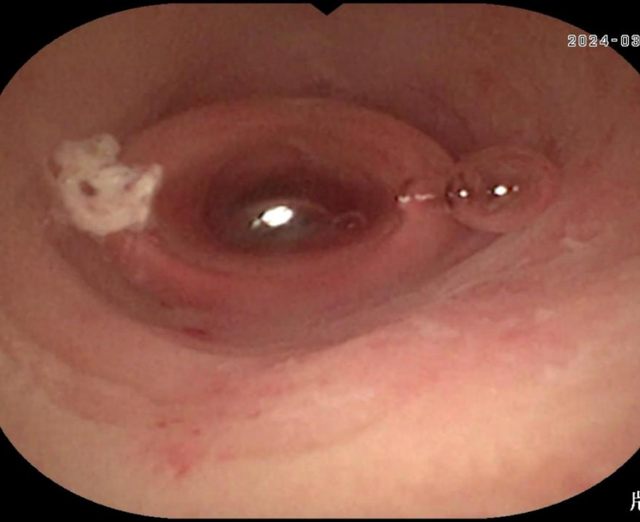

术中利用无痛肠镜技术到达阑尾开口,采用最新的“eyeMAX洞察”子母镜系统直视下进入阑尾腔内,通过冲洗、引流、网篮套取等操作,将嵌顿于阑尾腔内的粪石取出,术后患者腹痛明显缓解,1h后即可下地行走。次日顺利出院。

据徐宏伟主任介绍:内镜下逆行性阑尾炎治疗术是一种新型的内镜技术,经肠镜达到阑尾开口处,通过子母镜系统将超细的内镜探头置入阑尾腔内,直视下观察阑尾内部情况,并通过相关的器械(导管、网篮、支架等)对阑尾内的脓液、粪石进行处理,解除阑尾的梗阻,清除阑尾的炎症,是阑尾炎治疗的一种新型方式,相比外科手术而言,有着以下三大特点: